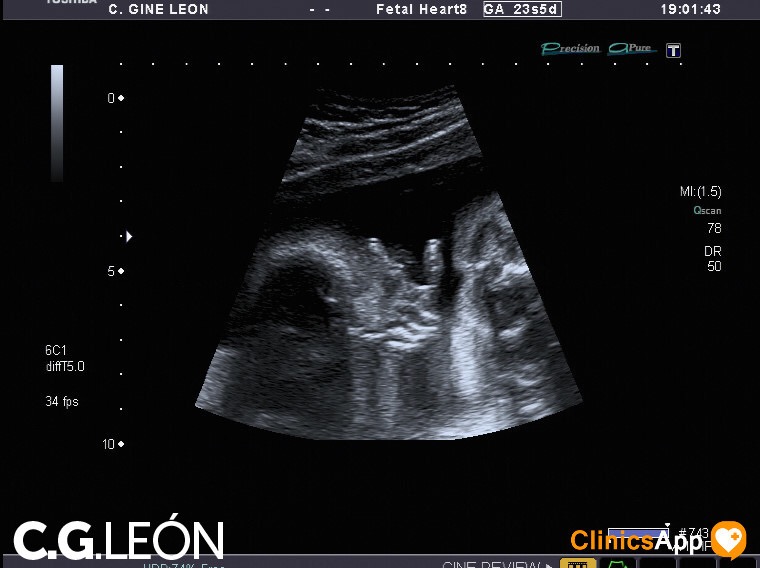

Aquí las fotos de la quinta ecografía, nada que destacar excepto que la ginecóloga estaba de mala leche y no se esmeró demasiado en las fotos. Hay una en la que se ve una mano, en directo se distinguía mejor, claro, porque se vio abierta como en la foto y luego la cerró. Pero por lo general encuentro de difícil interpretación este lote de fotos.